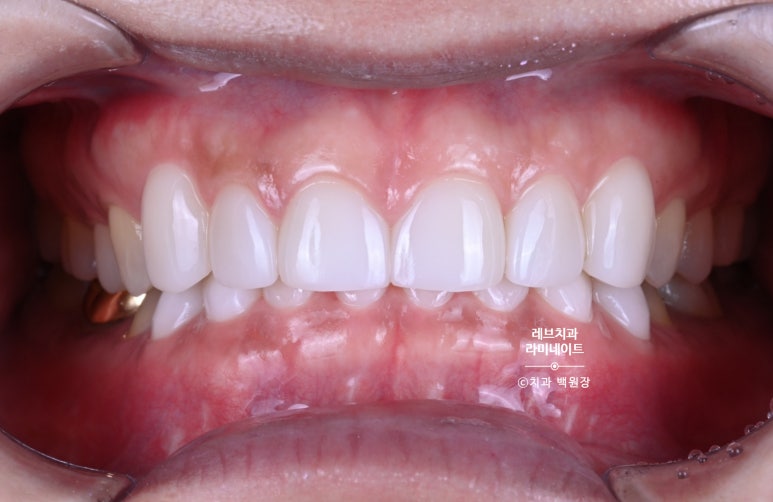

그래서 이렇게 마무리 된 상황!!!

환자분이 너무 너무 만족해하셨고, 더 나아가 치아의 시림 없이 모양도 단정하고 보강된 치아를 만들어드릴 수 있어서 상당히 보람된 케이스였답니다.

Before & After

약간의 잇몸성형을 통해 아랫니가 조금 더 보이게 함으로써 자연스러움을 추가하였습니다.

그리고 위 치아와 아래 치아 색상의 조화를 이루어 깔끔한 이미지를 가지실 수 있게 도와드렸습니다.

아래 앞니의 경우 신경치료 추가 없이, 치아가 시리지 않는 선에서 최소 삭제로 치료해드렸습니다.

길이를 단정하게 맞추고, 색상을 개선하니 정말 20년은 젊어보이는 느낌이 들더라구요.

이제 아래앞니 색상 때문에 치아미백을 하지 않아도 된다고 좋아하셨습니다.

웃어보시라 말씀드리니 조금 부자연스럽게 웃긴 하셨지만, 아래 앞니 치료에 대한 자신감으로 더 크게 웃게 되신 것을 보실 수 있을거에요.

레브네이트 치료 후 특징은 이제 더 자연스럽게 웃으실 수 있다는 것 !!

환자의 스마일을 찾아주는 치료입니다. 늘 자부심을 느끼며 치료하고 있습니다.